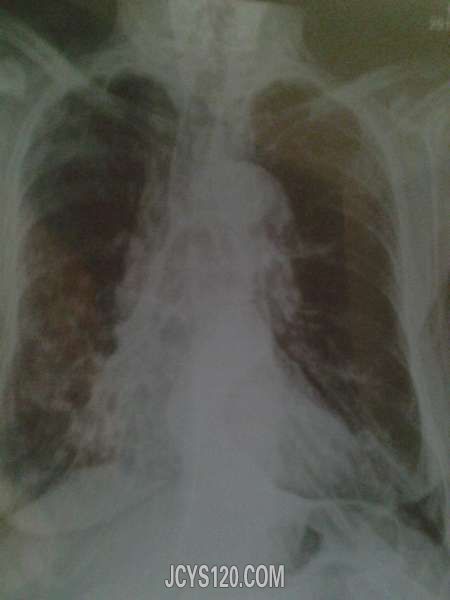

葛Xx 女 62岁 主诉 咳嗽咳痰一月余 现病史 患者一月前.无明显诱因出现咳嗽,无痰,在本诊所诊治.按支气管炎治疗.予以头孢替唑 安溴索 阿奇 喘定等分并输液四天.无效 咳嗽加重 .而转 ... 阅读全文>

患者四天前无意中发现左颈部有一肿物,无疼痛及其它不适,大小约1.*2CM,未经处理及就诊,四前后肿物体积增加三四倍,遂到我院就诊。经细问病史,患者称在今年2月份曾经有咳血一次,咳血后自行痊愈,无经处理 ... 阅读全文>